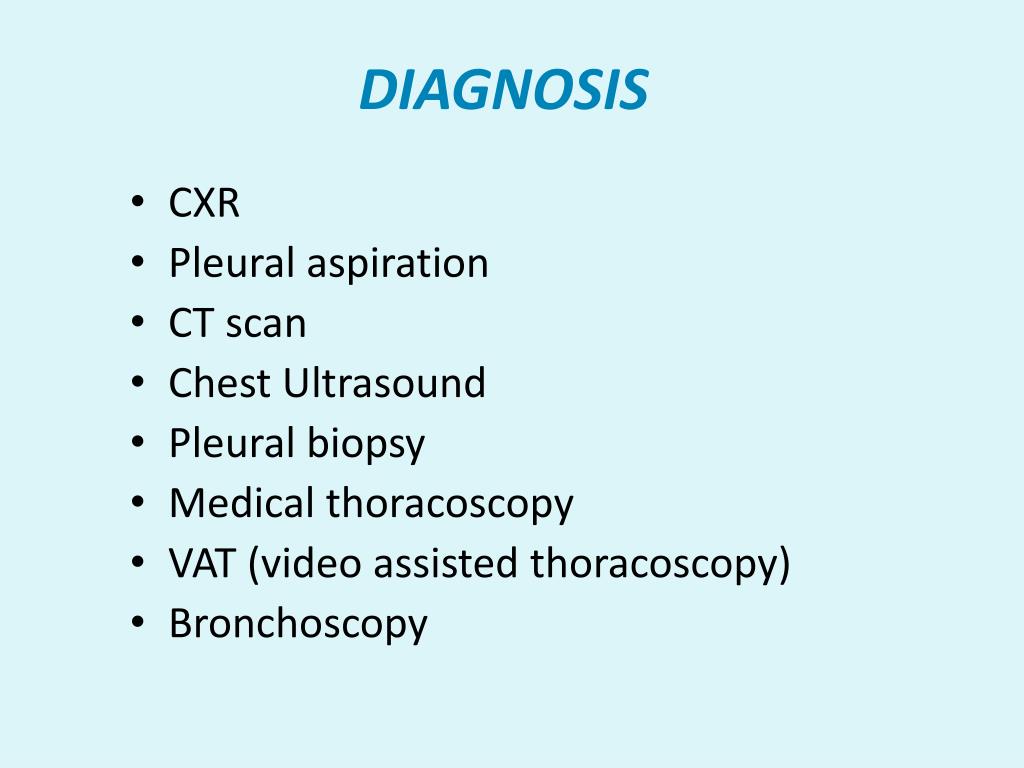

What is the diagnostic test for pleural effusion?

How is a malignant pleural effusion diagnosed?